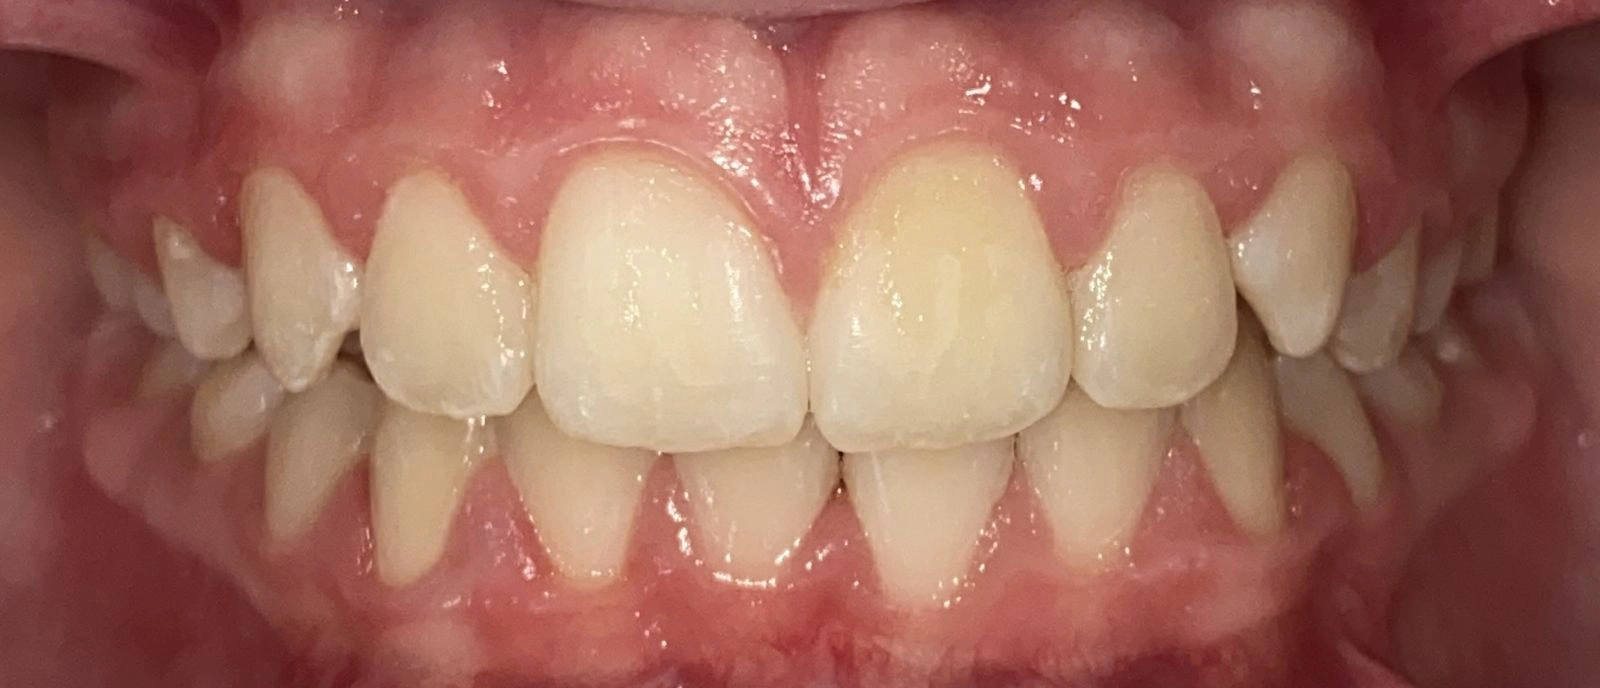

Actual Patient: Alexander

Alexander Before 4 Alexander After 4

Severe “Underbite”, Narrow Jaws, Adult Teeth Not Growing In

Alexander Before 1 Alexander After 1

Front View

Top View

Right & Left Sides

Front View Results

0 Month

6 Month

11 Month